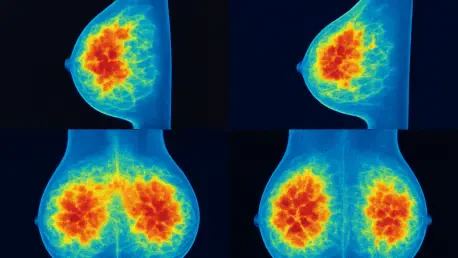

At its core, MaGNet operates by processing stained images of mammary tissue to trace branching patterns. Utilizing NetworkX software, it maps these structures as intricate networks, enabling detailed examination. The system automates the quantification of key metrics such as the total length of ductal trees, the number of ducts, alveoli (milk-producing units), and branching points, achieving a level of precision previously unattainable.

The results of MaGNet’s application to mouse models are striking. The software has proven capable of automating mammary gland branching analysis with remarkable accuracy, delivering reproducible quantitative data. Metrics that once took hours to compile manually are now generated swiftly, providing a reliable foundation for scientific inquiry.

Compared to traditional approaches, MaGNet excels in capturing the nuanced details of mammary architecture. Where manual methods often missed subtle variations or struggled with consistency, this tool offers a comprehensive view of the gland’s structure. Such precision is vital for understanding the complex interplay of factors shaping breast tissue development.